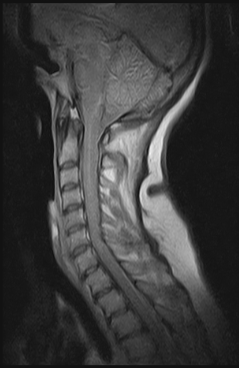

Ressonância Magnética para Coluna Cervical

RM BrasilProcurando sobre ressonância magnética para coluna cervical? Na RM Brasil, todos os pacientes são tratados com dedicação e atendimentos humanizados.Comprometimento, eficiência e virtude são nossas...